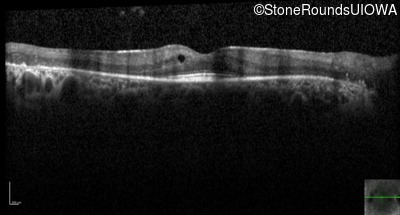

Optical Coherence Tomography - Right - 20/32

Exemplar / OCT Stack

OCT Stack